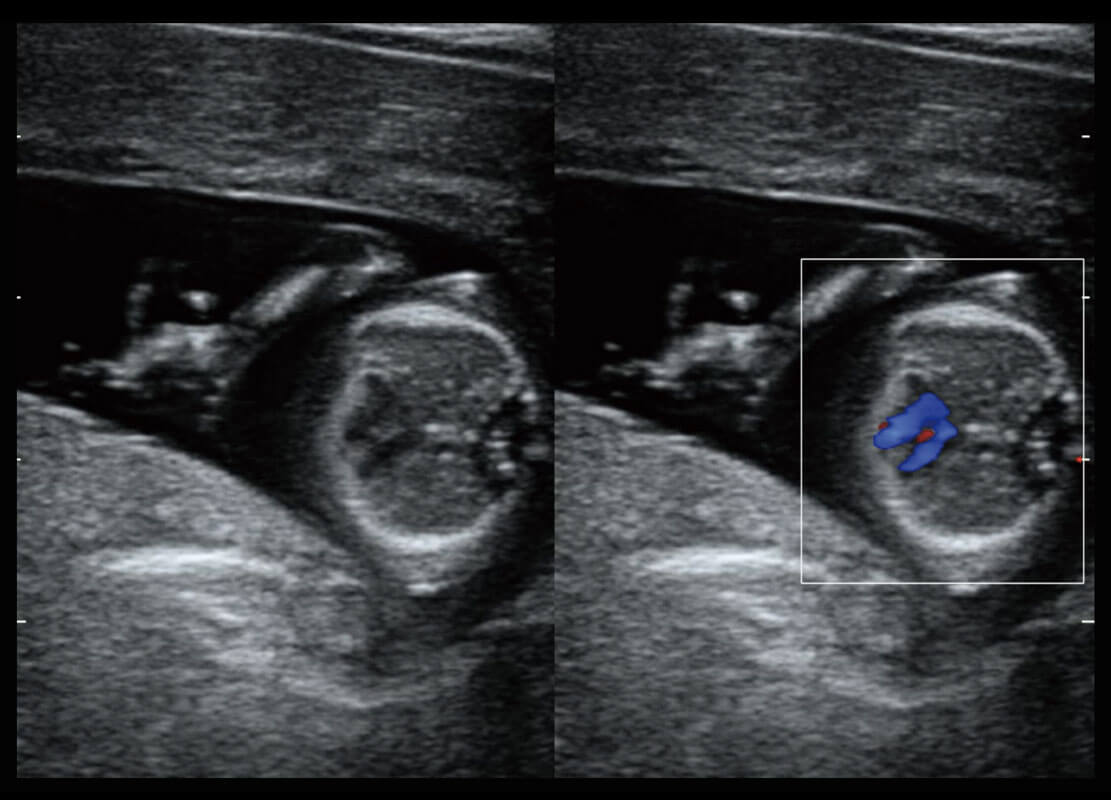

P60在胎儿早孕期超声筛查中为您带来优异的图像质量。

早孕-胎心